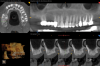

Fig 12. CBCT of final implant placement with

cross-section of maxillary left side sinus elevation.

CBCT evaluation indicated that all four implants were healthy, and a decision was made to place two more implants. The plan called for one implant to be placed on each side to create an all-on-six solution. In the maxillary right quadrant, an implant would be placed between the two existing implants. The complexity of maintaining 3 mm of adequate space between each implant in the right quadrant for hygiene maintenance and adequate blood supply necessitated the use of guided surgery, as failure to maintain the 3 mm inter-implant spacing can result in severe bone loss and peri-implantitis.19In the left quadrant an implant was planned posterior to the most distal implant, thus requiring the implementation of the OD sinus lift protocol described in Case 1 (Figure 10).

Using the TAP method for calibration, the existing implants were used as markers for the navigational unit (Figure 11). Full-thickness flaps were elevated on both planned implant site locations. Pilot drills and all subsequent drills were calibrated for navigational surgery. Two implants were placed with adequate torque of 40+ Ncm and ISQ values of 80 and 79, respectively, enabling second staging of implants with healing abutments (Figure 12). The surgical sites were sutured and allowed to heal.